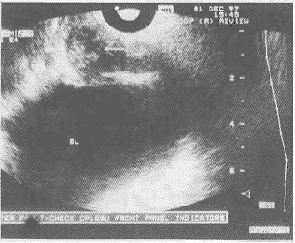

图4 TRUS前列腺低超声结节

TRUS是80年代后期Lee等报道了其在PCa方面的显著性价值后广泛运用于临床的,是目前PCa诊断的最佳影像学方法,远优于CT、MRI等[6]。TRUS可准确了解肿瘤的三维图像,可测量前列腺及肿瘤的体积。Marton等认为治疗前了解前列腺中肿瘤的体积可提供影响治疗方案和预后的重要信息。其敏感性为52%~91%,本组PCa中TRUS阳性率为69.6%。

PSA≤4.0ng/ml3例(13.0%),4.0~10.0ng/ml8例(34.8%),10.1~20.0ng/ml7例(30.4%),>20ng/ml5例(21.7%)。DRE发现结节6例(26.1%),坚硬改变8例(34.8%),不规则改变5例(21.7%),正常4例(17.4%)。TRUS发现低超声结节改变10例(43.5%),钙化不均匀改变6例(26.1%),高超声改变2例(8.7%),正常5例(21.7%)。当联合运用此三种方法时除1例外均能发现有异常改变,见表1~3,图4。表1 DRE及TRUS检查结果的PSA分布